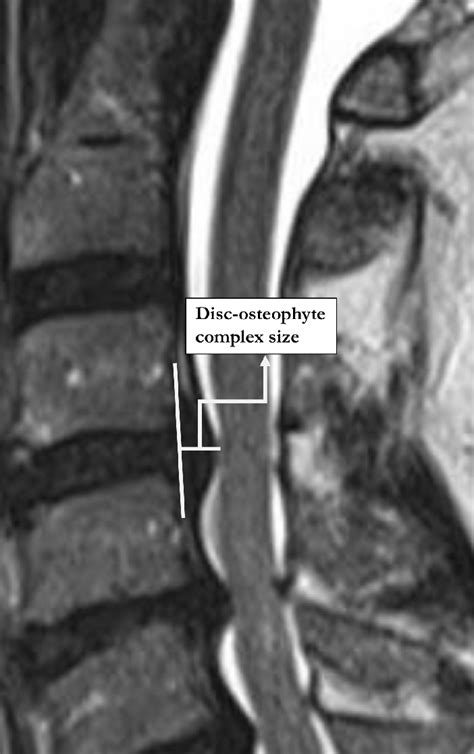

Illustration of disc-osteophyte complex size measurement. | Download ...